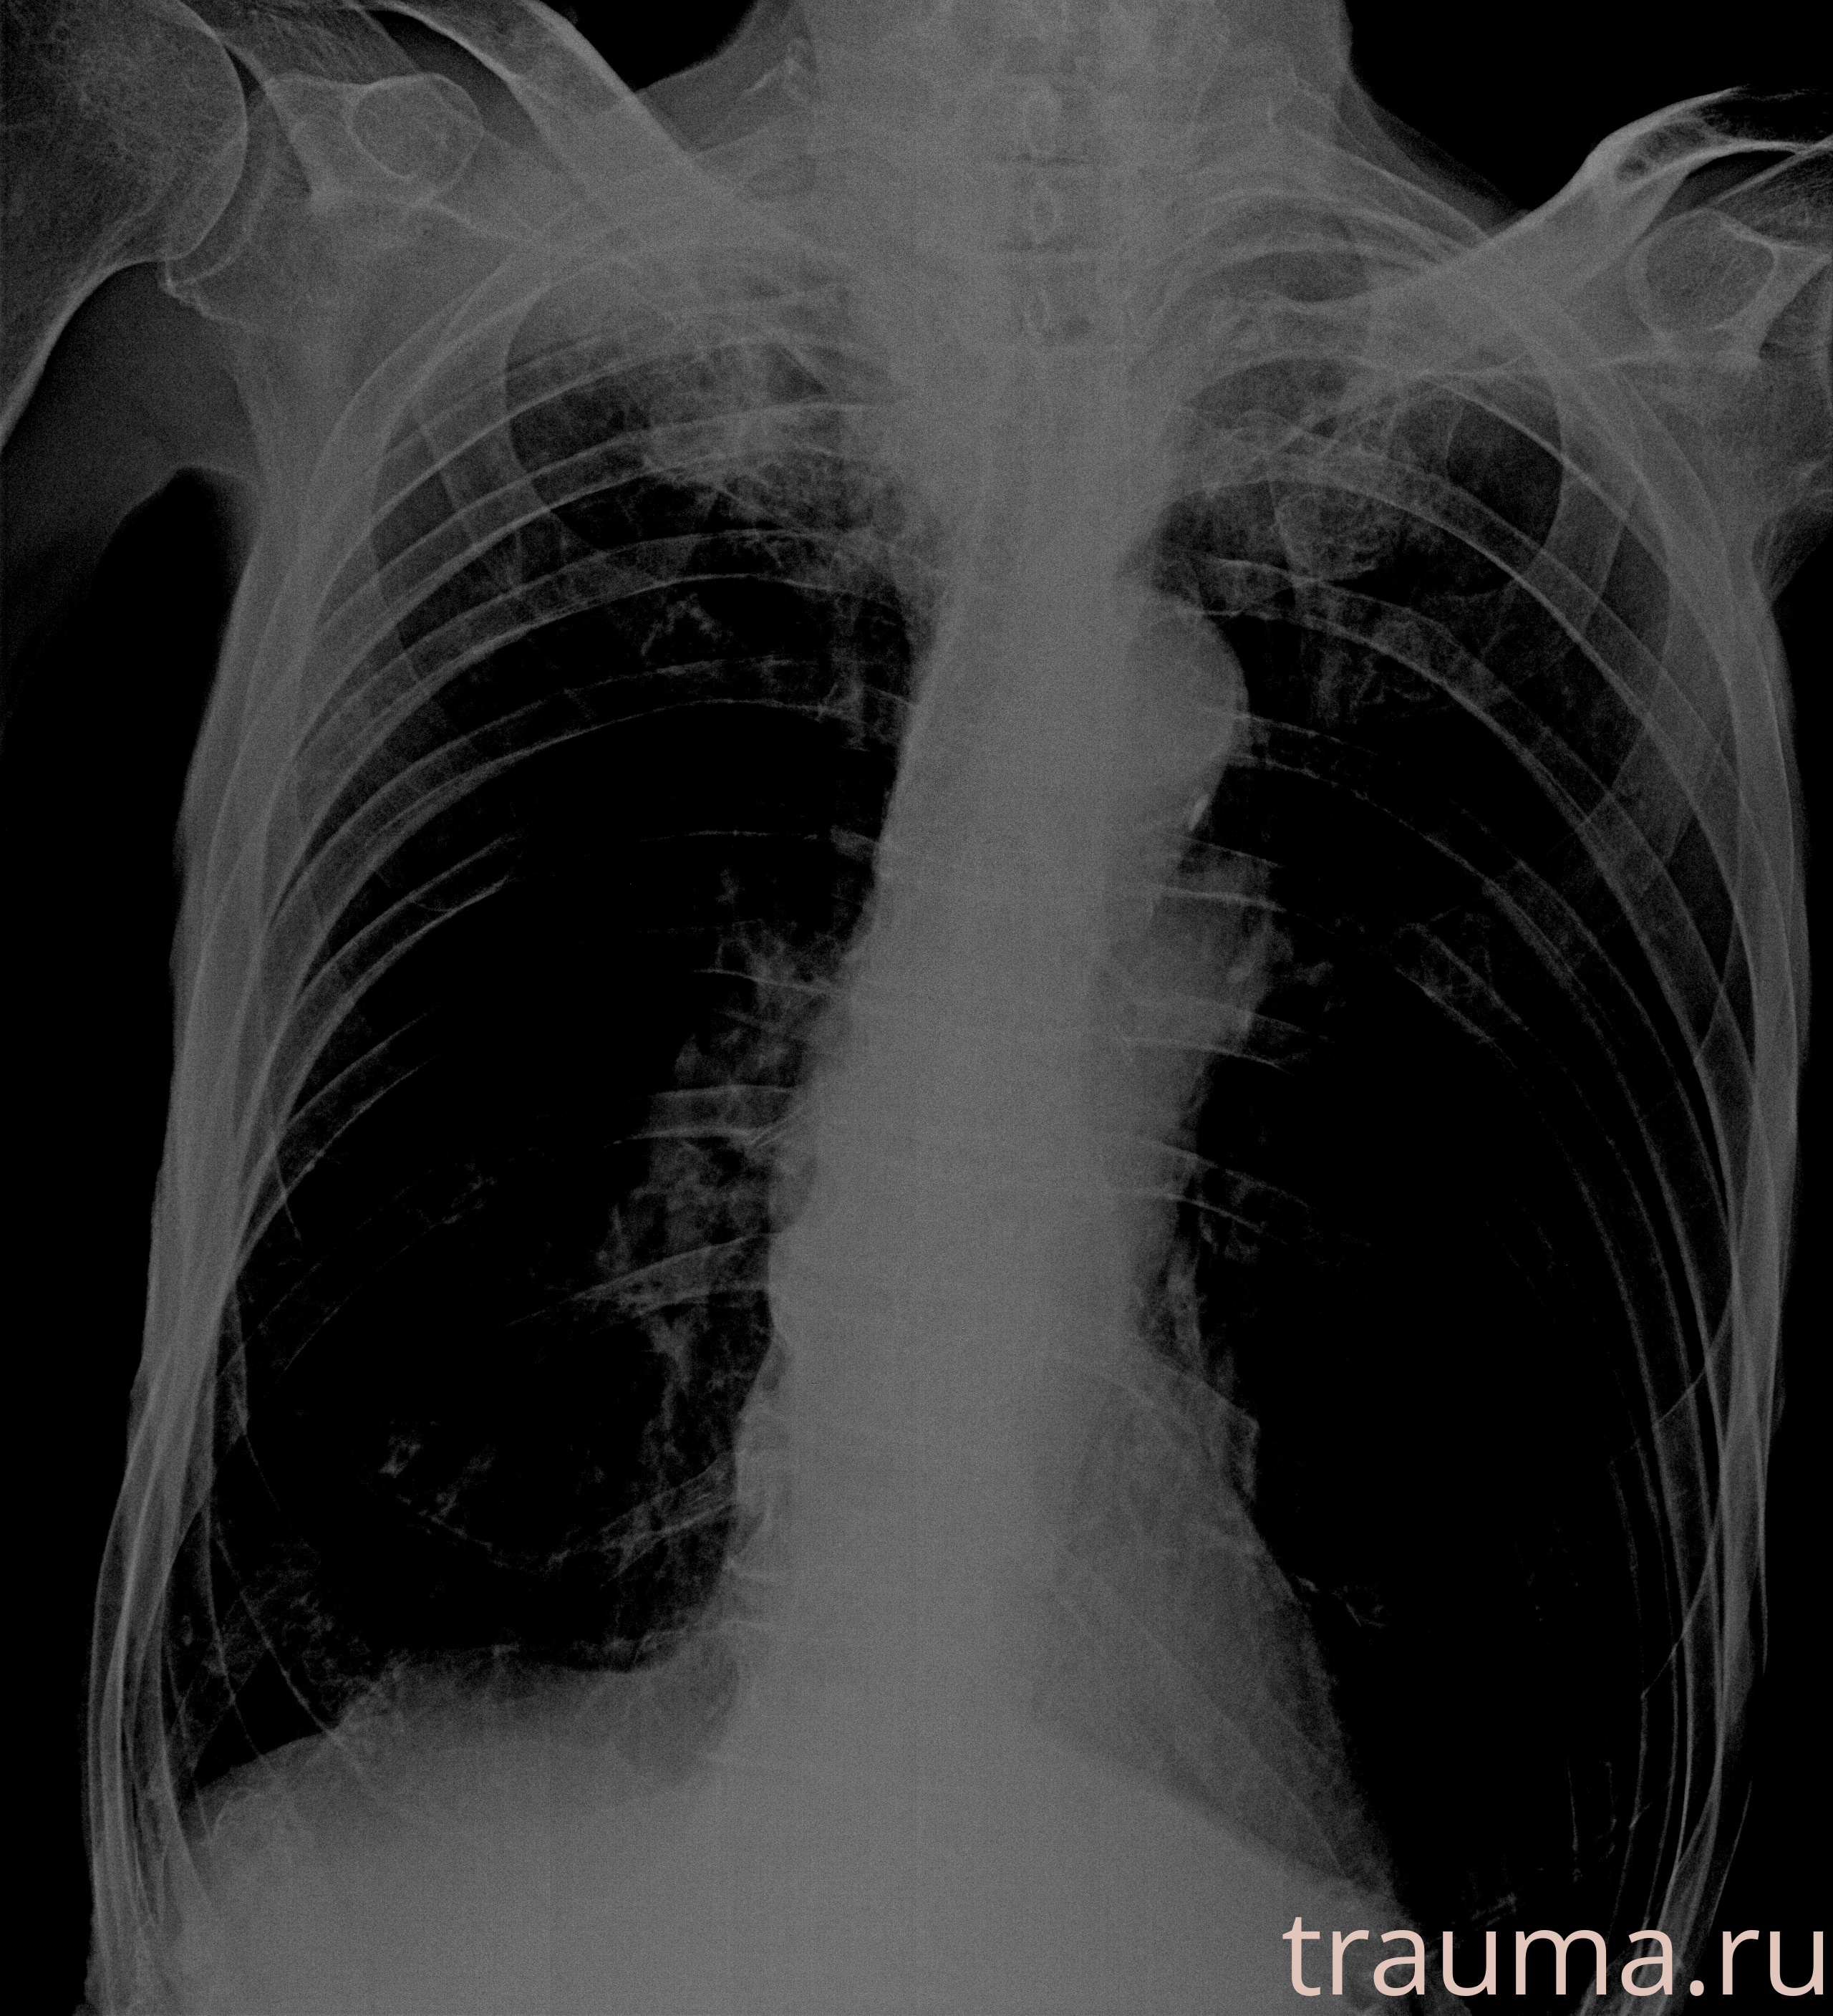

Рентген на дому: по вашему адресу приезжает врач-рентгенолог, травматолог-ортопед с мобильным рентгеновским аппаратом, проводит диагностику травмы или заболевания, делает необходимые рентгенограммы, дает рекомендации по дальнейшему лечению. Получить качественные снимки в домашних условиях возможно благодаря уникальной методике, разработанной МосРентген Центром для института  Склифосовского